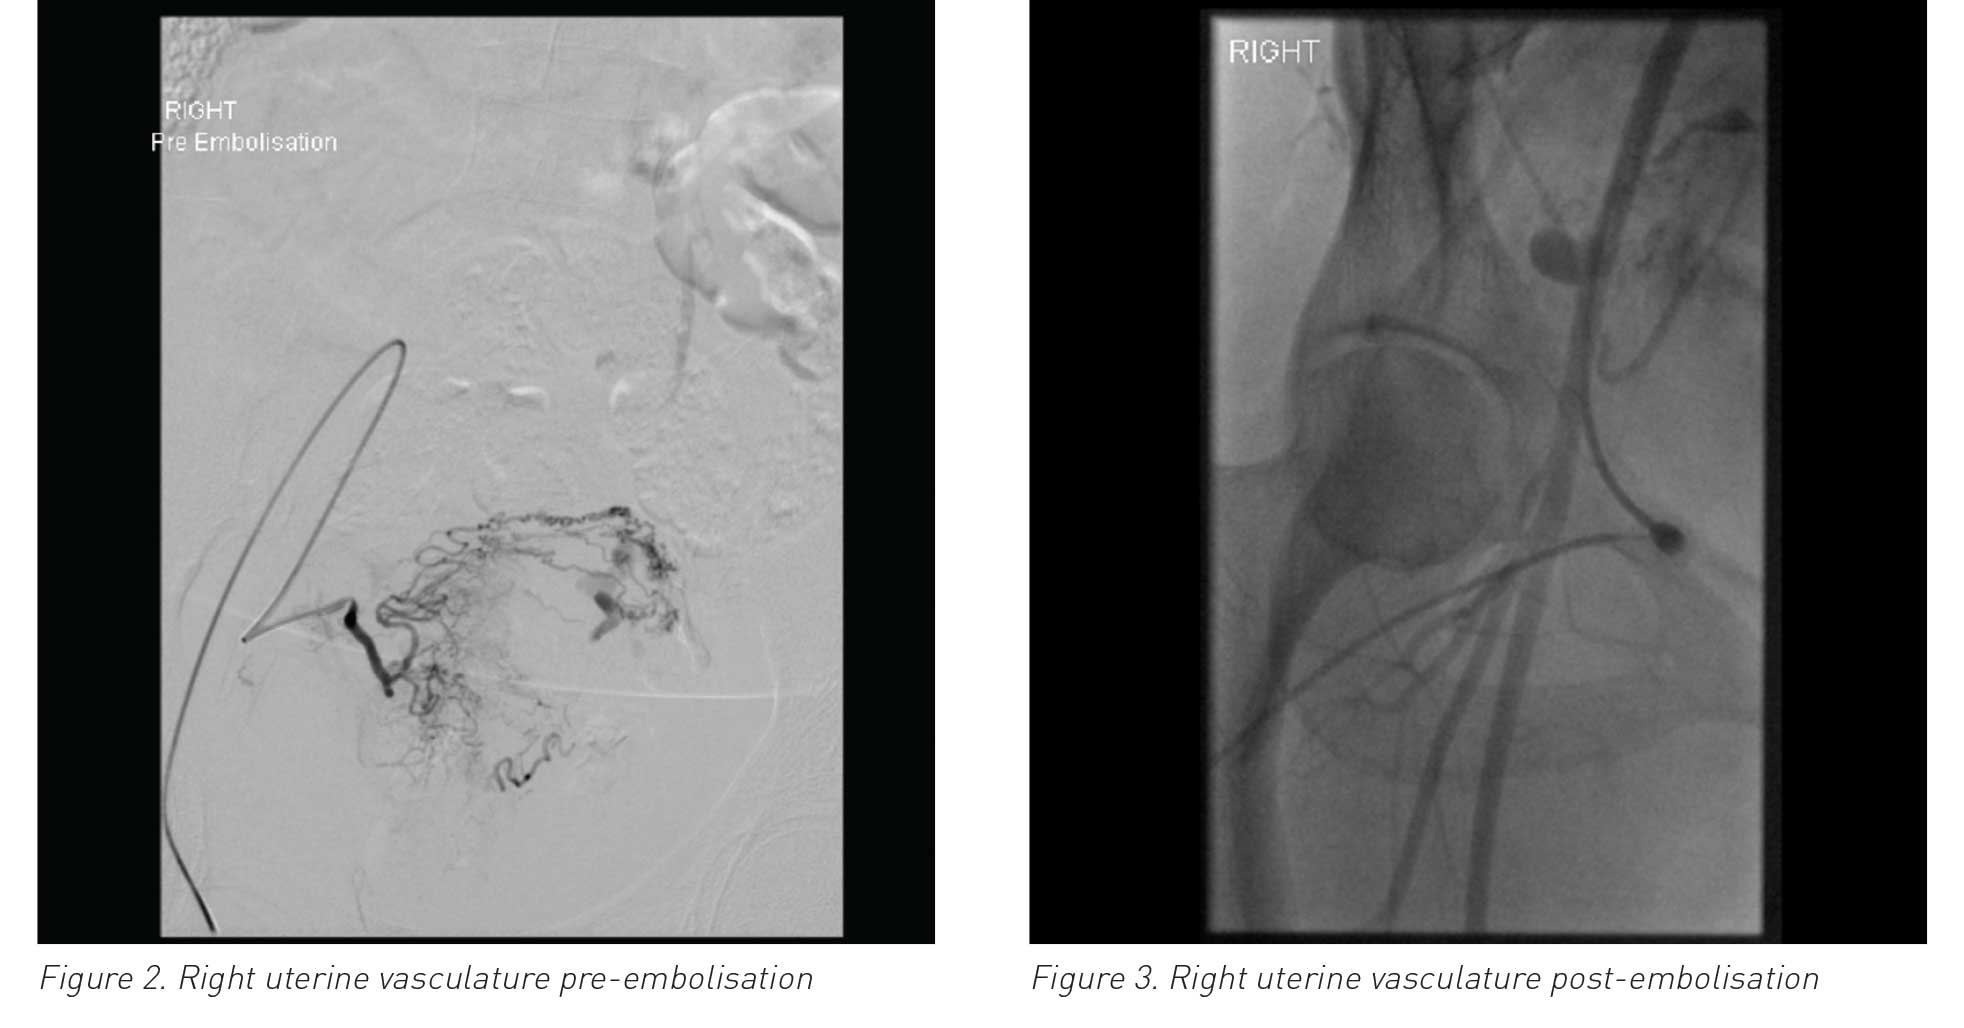

Uterine arteriovenous malformation (AVM) is defined as abnormal and nonfunctional connections between the uterine arteries and veins. Although rare, it is a potentially life-threatening condition. Fewer than 100 cases are reported in existing literature and include patients who presented with per vaginam (PV) bleeding, often mild to moderate, but sometimes life-threatening. It is likely to occur during a woman’s reproductive years and treatment depends on signs and symptoms, as well as future fertility requirements. If symptoms are not improved with conservative treatment, uterine artery embolisation is required to avoid the need for a hysterectomy.

This report looks at a case of acquired uterine AVM, confirmed by angiography, which was successfully treated with bilateral uterine artery embolisation.

There are two types of AVM in the uterus: one is congenital and the other is acquired through previous uterine trauma (eg. curettage or previous pelvic operations), infection or trophoblastic disease. Congenital AVM is extremely rare, whereas acquired AVM is increasing in incidence. This rare condition occurs most frequently in women of reproductive age. Such women present most commonly with PV bleeding but some present with life-threatening bleeding. Management of AVM is mostly conservative but may necessitate embolisation.

A 30-year-old female (P3+1) presented at the emergency department at 6+ weeks gestation with mild pain and PV bleeding; following a scan, she was discharged home. She subsequently presented at the early pregnancy assessment unit (EPAU) for a further scan to confirm dates and the viability of her pregnancy. She was diagnosed with a missed miscarriage at 7+3 weeks and a plan was made for medical management. She received mifepristone and full doses of misoprostol, neither of which had any effect for two days. She was then booked for an evacuation of retained products of conception (ERPC). Her haemoglobin (Hb) levels were 12g/dl. During the ERPC, she bled > 2 litres within 25 minutes and required four units of blood transfusion.

(click to enlarge)